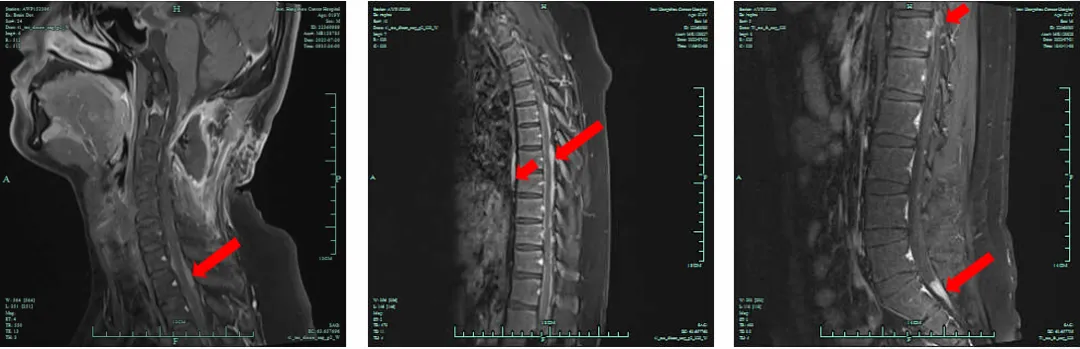

2022年8月23日,复查脊髓MRI,疗效评价为部分缓解(PR);双下肢肌力5级。

图3.放疗末期复查脊髓MRI检查结果(2022.8.23)